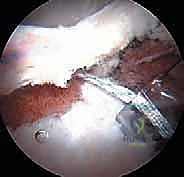

الخطوة 3: الاستكشاف بكاميرا 4K

يتم إدخال منظار مزود بكاميرا عالية الدقة (4K) وإضاءة قوية. تُعرض الصورة مكبرة على شاشة أمام الجراح، مما يسمح له برؤية أدق تفاصيل الغضروف والشفا الحقي بوضوح يفوق الرؤية بالعين المجردة.

الخطوة 5: إصلاح الشفا الحقي (Labral Repair)

إذا كان الشفا الحقي ممزقاً (وهو أمر شائع جداً)، لا يتم استئصاله، بل يحرص الدكتور هطيف على إصلاحه للحفاظ على وظيفة المفصل. يتم ذلك باستخدام "خطاطيف خياطة" (Suture Anchors) صغيرة جداً تُزرع في العظم وتُستخدم لربط وخياطة الشفا وإعادته لمكانه الطبيعي.